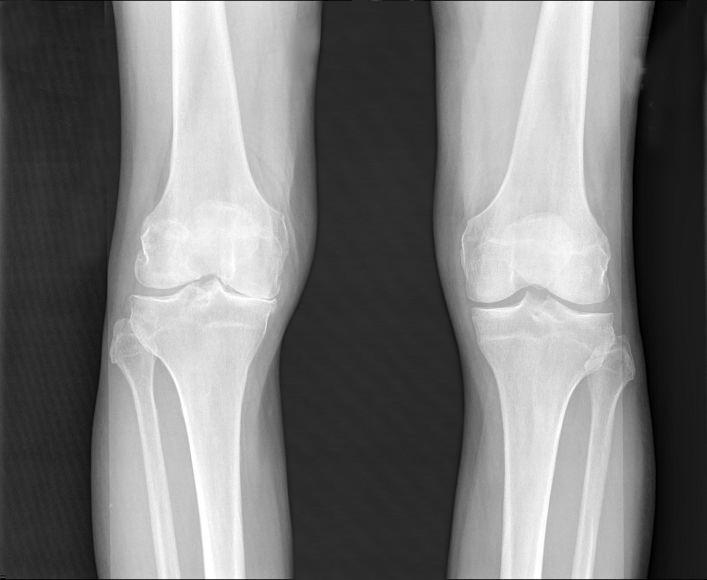

"Patients are frequently in pain by the time osteoarthritis is diagnosed. The imaging tests most frequently used, X-rays, don't indicate the level of pain or allow us to directly see the amount of cartilage loss, which is a challenge for physicians and patients," said co-first author Averi A. Leahy, B.A., an M.D./Ph.D. student in the medical scientist training program at TUSM and the Sackler School.